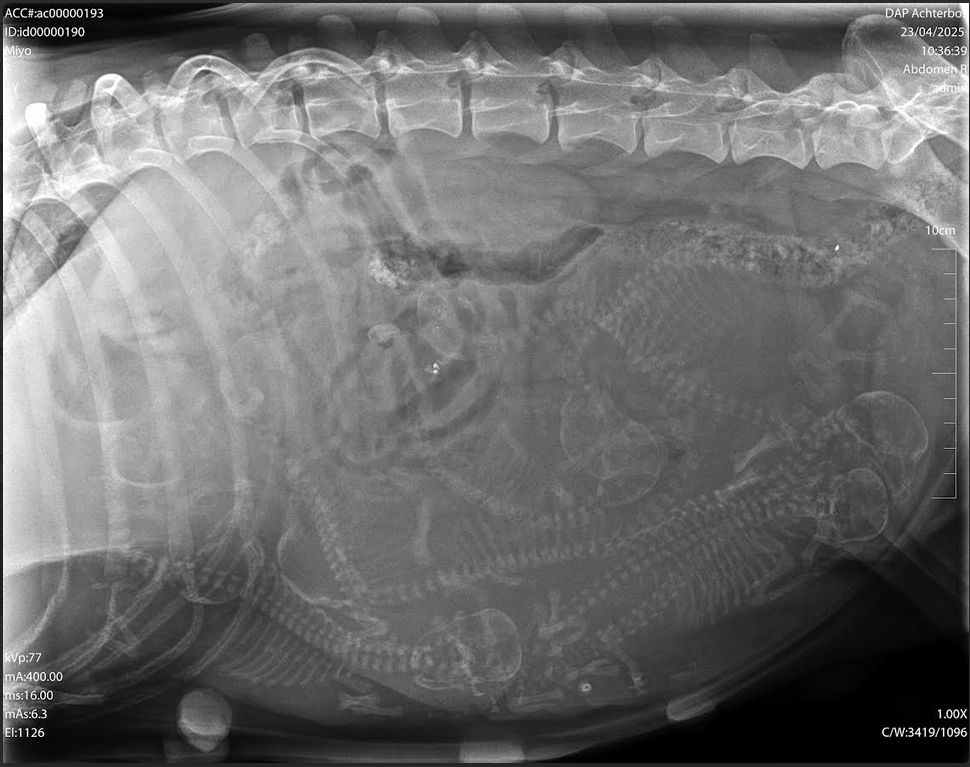

Een week voor de uitgerekende datum ( 23 april ) wordt een röntgenfoto ( RX ) gemaakt en krijgen we een beter beeld van het aantal pups dat zal verwacht worden.

De RX is ondertussen gemaakt. De dierenarts wist ons te vertellen dat er minimaal 8 pups op zitten. Misschien wel 9, dit is niet helemaal duidelijk op de foto te zien.

Hieronder vind je de RX terug die gemaakt is op woensdag 23 April 2025.

Op de röntgenfoto kan je de skelletjes van de pups tellen.